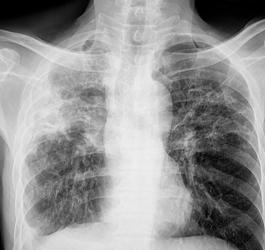

- Pulmonologia